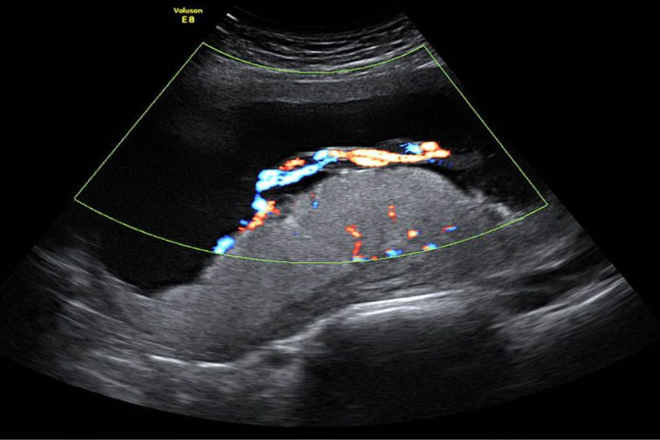

Pertinencia de la Ecográficamente Volumen estimado de líquido amniótico.

El líquido amniótico proporciona un ambiente ideal para el normal fetal crecimiento y el desarrollo. Se proporciona el feto con una fuente de agua, protege al feto de trauma, permite movimientos normales crítico para el desarrollo anatómico, y contribuye al desarrollo de los pulmones fetales. Las características fisiológicas de la dinámica en el volumen de líquido amniótico (AFV) son complejos y no se entiende claramente. Para entender la AFV, el conocimiento de las rutas de movimiento potencial del líquido amniótico y los mecanismos reguladores implicados deben ser tomados en consideración. Hay varias fuentes potenciales que influyen en el AFV: la producción de orina fetal, deglución fetal, la secreción de líquido pulmonar fetal, la vía intramembranosa (movimiento de agua y solutos entre amniótico sangre y fluido fetal y de la placenta), la vía transmembranosa  (movimiento del agua y solutos a través de la superficie del amnios y el corion), secreciones de la fetales oral-nasal y la circulación de agua a través de la piel altamente permeable durante la gestación temprana.

La producción de orina fetal es la fuente predominante de liquido amniótico en la segunda mitad del embarazo, como lo demuestra la casi completa ausencia de líquido amniótico en el caso de agenesia renal o la obstrucción del tracto urinario fetal. La primer Orina fetal entra en el espacio amniótico en la gestación de 8 a 11 semanas y constantemente aumenta durante la gestación.

La producción por kilogramo de peso corporal fetal a las 25 semanas es de aproximadamente 110ml / kg cada 24 horas, y es aproximadamente 190 ml / kg por 24 horas a 39 semanas. Estimaciones de salida de la orina humana fetal se han hecho a partir de estudios sonográficos de la vejiga fetal medido a intervalos regulares. La mejor estimación de la orina fetal a término es de 700 a 900 ml por día. El feto es capaz de responder a los cambios en el estado del líquido